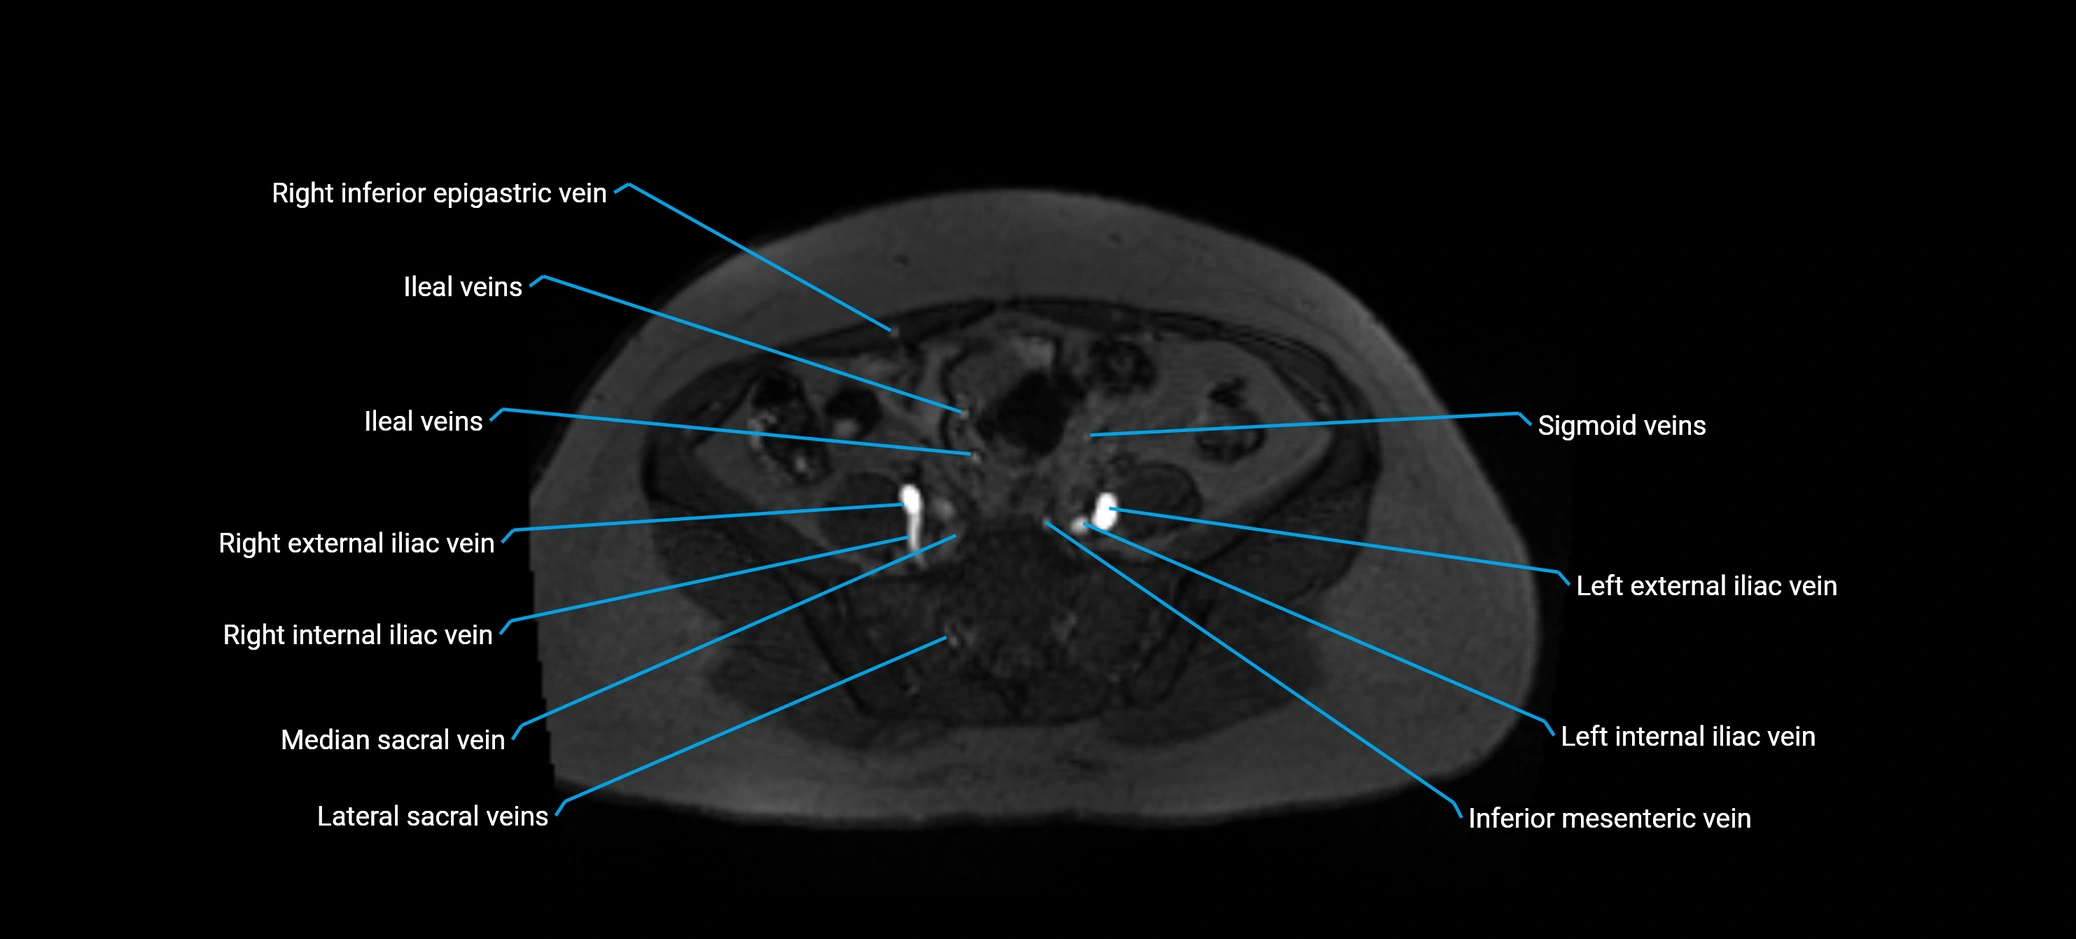

image